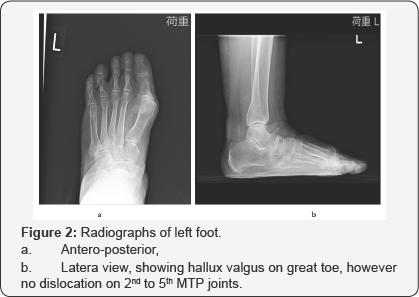

She had undergone treatment with a total contact insole on her left foot for several months at another hospital, recognized it as planter callosities, but the painful symptom did not improvement. At our hospital, we performed some radiological examinations. X-ray images of her left foot showed that hallux valgus of the great toe, hallux valgus angle (HVA) was 27°, but 2nd to 5th MTP joints did not recognize subluxation (Figure 2). Plain CT revealed the subcutaneous mass below the left 1st MTP joint that well capsulated mass with similar to water density (Figure 3).